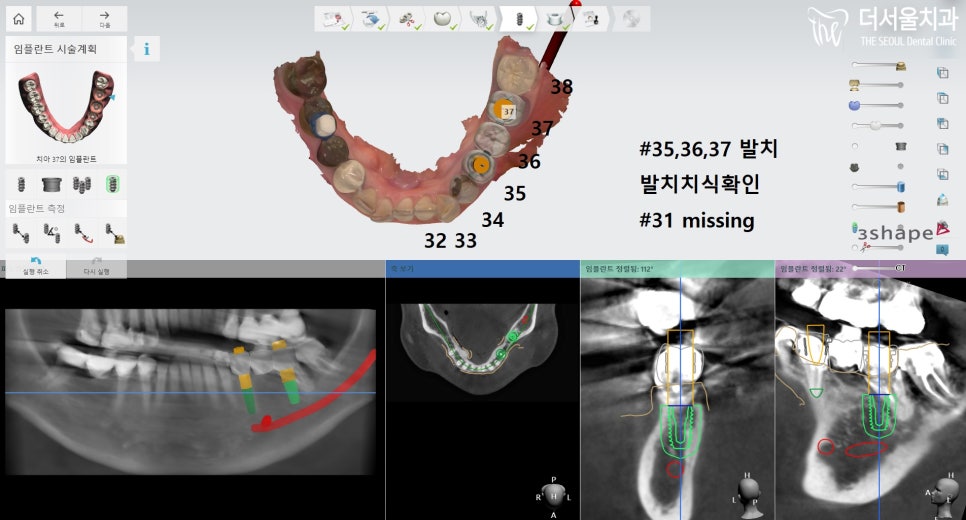

발치 전 컴퓨터 분석을 통해

임플란트 식립 계획을

수립하였는데요.

다행스럽게도 뼈이식을

진행하지 않아도 되었기에